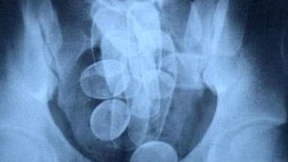

Er wollte Kokain in 60 Behältern im Körper durch den Frankfurter Flughafen schmuggeln. Das misslang. Nun hat der Drogenschmuggler vom Landgericht die Quittung bekommen.